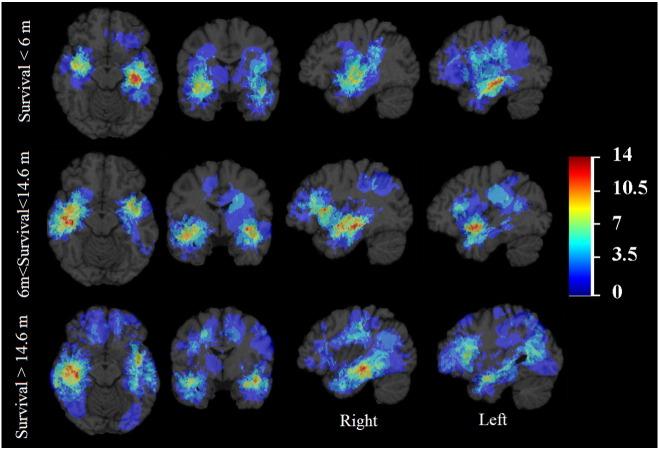

Survival of glioblastoma in relation to tumor location: a statistical tumor atlas of a population-based cohort.胶质母细胞瘤的生存与肿瘤位置的关系:基于人群队列的统计肿瘤图谱

Acta Neurochir (Wien). 2021 Jul;163(7):1895-1905. doi: 10.1007/s00701-021-04802-6. Epub 2021 Mar 20.